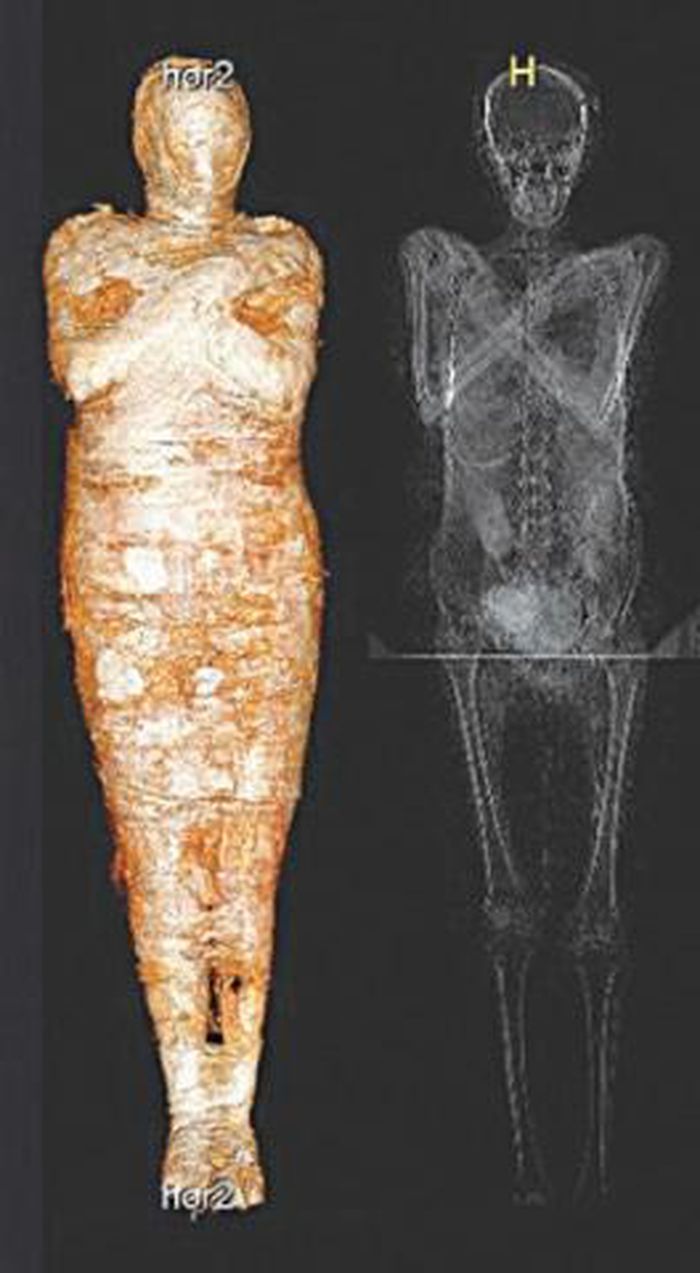

Được lưu giữ trong Bảo tàng Quốc gia ở Warsaw, Ba Lan từ năm 1917, một xác ướp Ai Cập cứ ngỡ thuộc về linh mục nhưng thực tế là của một thai phụ.

Vào năm 1826, một xác ướp Ai Cập và quan tài được tặng cho Đại học Warsaw, Ba Lan. Sau đó, chúng được lưu giữ và bảo quản trong Bảo tàng Quốc gia ở thành phố Warsaw kể từ năm 1917.

Theo các chuyên gia, xác ướp có niên đại hơn 2.000 năm tuổi. Trong suốt nhiều năm, họ cứ ngỡ đó là thi hài của một linh mục Ai Cập cổ đại tên là Hor-Djehuty.

Tuy nhiên, bí mật "động trời" về giới tính của xác ướp trên được hé lộ khi các chuyên gia sử dụng kỹ thuật chụp cắt lớp vi tính vào năm 2016.

Kết quả cho thấy xác ướp không phải là của linh mục Hor-Djehuty. Thay vào đó, thi hài thuộc về một phụ nữ tử vong khi mang thai. Thai nhi đang ở tuần thai thứ 26 - 30.

Sau khi tử vong, thai phụ trên được ướp xác cùng với bào thai trong bụng. Từ đây, các chuyên gia đặt ra hàng loạt câu hỏi như: người phụ nữ này là ai? Tại sao bà được ướp xác cùng với thai nhi?...

Trước sự việc này, nhà khảo cổ học Wojciech Ejsmond thuộc Học viện Khoa học Ba Lan cho biết bào thai đã không được lấy ra khỏi bụng mẹ như trong quá trình ướp xác thông thường.

Chính vì vậy, tính đến thời điểm hiện nay, đây là xác ướp duy nhất được ướp xác với thai nhi nguyên vẹn trong bụng mẹ.

Thai phụ này được ướp xác rất cẩn thận với một bộ bùa hộ mệnh. Điều này cho thấy bà xuất thân từ tầng lớp giàu có hoặc có địa vị cao trong xã hội.